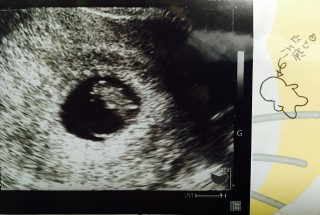

胎嚢が通常より大きく、11週相当と言われました。赤ちゃんも卵黄嚢からかなり離れた場所にいたのでかなり心配しましたが、母子手帳をもらうことになったので一安心。

10年ほど前、流産してしまってからの妊娠です。 先生から、少し大きいですね、順調です。と言われました! このまま、順調に育ってほしいな。

前回の時は、心拍が確認出来なくて、また2~3週間後に来てくださいと、言われて不安でしたが、 心拍も確認出来て『母子手帳もらいに行って来てね』と言われた時は安心しました🎵3人目の妊娠ですが、元気に育ってもらいたいです🎵CRL=17.2㎜